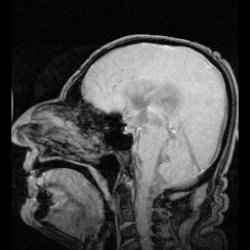

Ликвор образуется в мозге: в эпендимальных клетках сосудистого сплетения (50—70 %), вокруг кровеносных сосудов и вдоль желудочковой стенки. Далее цереброспинальная жидкость циркулирует от боковых желудочков в отверстие Монро (межжелудочковое отверстие), затем — вдоль третьего желудочка, проходит через Сильвиев водопровод. Затем проходит в четвёртый желудочек, через отверстия Мажанди и Лушки выходит в субарахноидальное пространство головного и спинного мозга. Ликвор реабсорбируется в кровь венозных синусов и через грануляции паутинной оболочки.